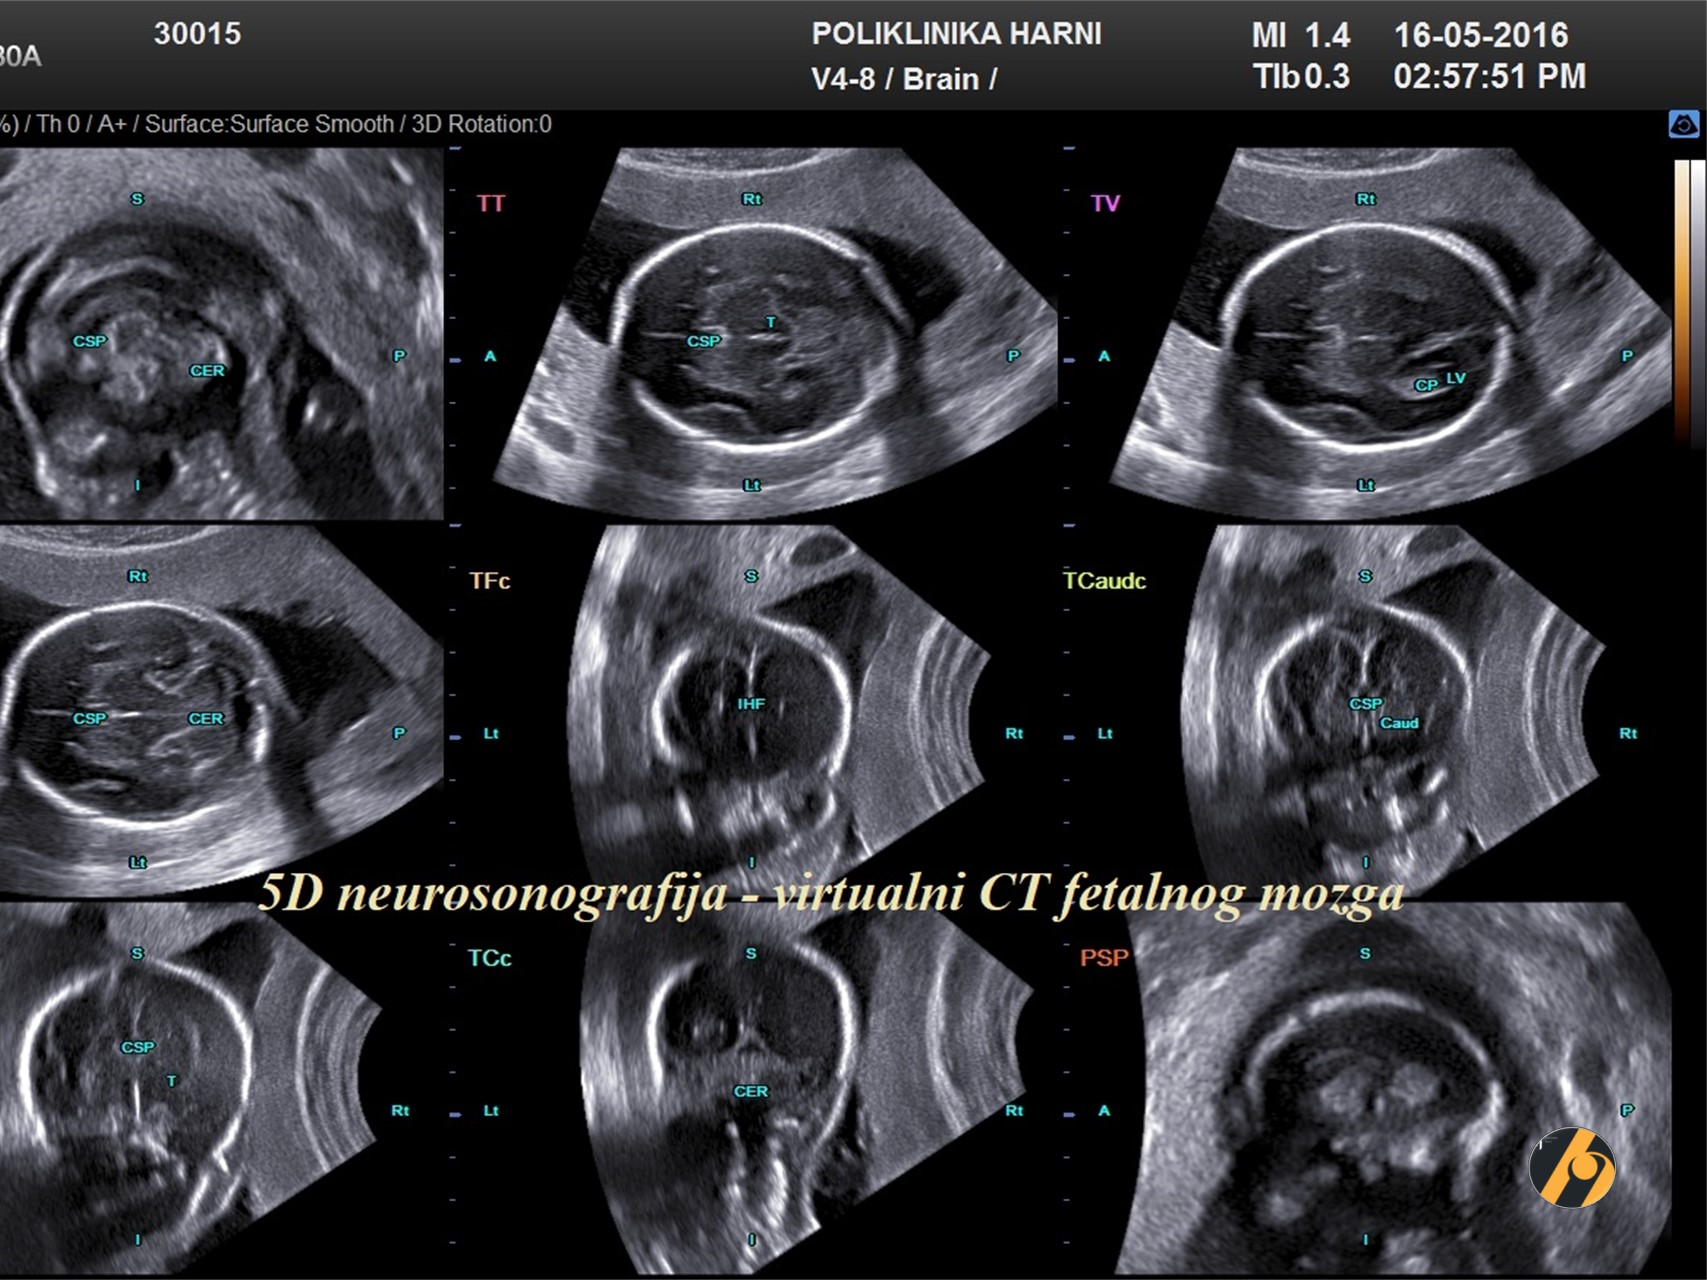

Anatomski presjeci

U ovo vrijeme vidljivi su svi vitalni organi, a njihova veličina dopušta preciznu procjenu izgleda i otkrivanje eventualnih odstupanja. Većina organa je u ovo vrijeme tako razvijena, da se ultrazvučnim putem može dobro procijeniti njihova morfologija, građa i struktura. Osobiti značaj pridaje se pregledu razvijenosti središnjeg živčanog sustava, zatvorenosti kralješnice i fetalnoj ehokardiografiji, pregledu fetalnog srca. Novije tehnologije pruža svojim mogućnostima detaljne prikaze ovih organa, osobito 5D ultrazvuk koji automatski generira seriju najvažnijih presjeke organa koji se promatra u sve tri dimenzije.

Mozak

Postoje tri ravnine u bazičnom ultrazvučnom pregledu koje je potrebno prikazati: transventrikularna, transtalamička i transcerebelarna. Anatomske strukture koje su dio standarrnog pregleda su:

- Lateralni ventrikuli; prednji rogovi lateralnih ventrikula koji su odvojeni cavumom septi pellucidi; u stražnjim rogovima prikaz ehogenog pleksusa choroideusa te mjerenje debljine lateralnih ventrikula na nivou pleksusa choroideusa radi procjene količine cerebrospinalne tekućine.

- Cavum septi pellucidi; u mediokoronalnom presjeku se prikazuje prekid kontinuiteta interhemisferične fisure korpusom kalozumom te cavum septi pelucidi ispod korpusa kalozuma, jasno odvojen od prednjih rogova lateralnih ventrikula.

- Falx cerebri.

- Talamus.

- Cerebellum i vermis koji s 20 tjedana gestacije odvaja četvrtu komoru i cisternu magnu. Prije 20. tjedna postoji prirodna komunikacija između četvrte komore i cisterne magne, a nakon 20. tjedna su odvojene vermisom. U slučaju perzistencije komunikacije, postoji sumnja na Dandy-Walker malformaciju.

- Uredno formirana Silvijeva fisura i parijeto-okcipitalni sulkus su znak primjerenog razvoja giracije za ovu gestacijsku dob.